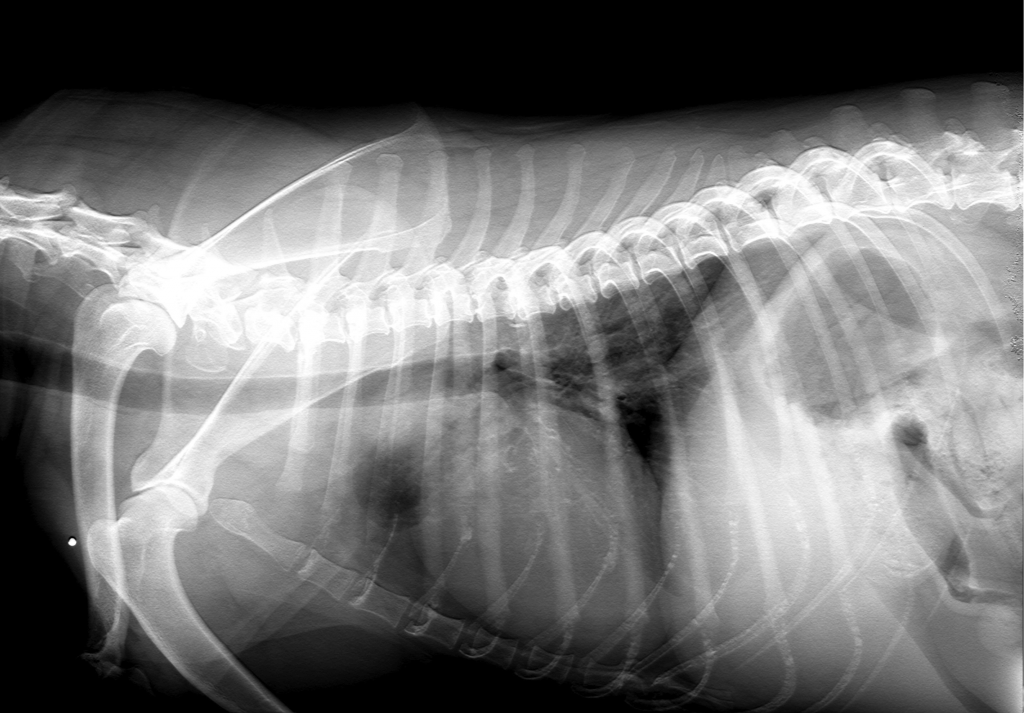

Radiographie thoracique:

Visualisation de la trachée, des poumons, du coeur, etc…